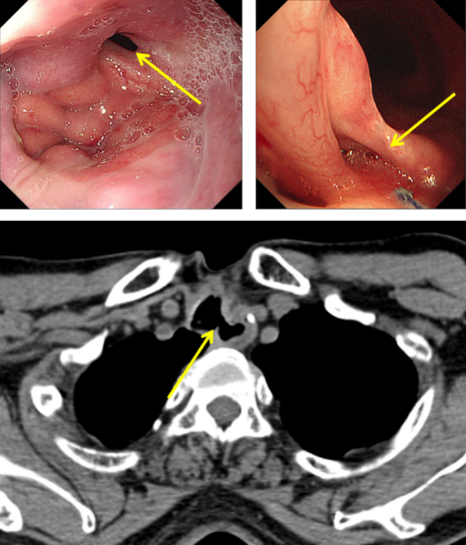

图1:气管食管瘘口

经推荐,老秦慕名来到我院胸外科胡杨副主任医师处就诊。经检查发现,老秦的病情与其他气管食管瘘患者相比,更为复杂和严重:一是瘘口所处位置较为“刁钻”。患者气管食管间瘘口位于颈胸交界部位,无论是从颈部或是胸部入路均难以充分暴露瘘口;二是瘘口情况较为糟糕。该患者于外院多次行瘘口修补手术,瘘口附近势必粘连严重、组织结构难以辨认,损伤喉返神经、颈胸部血管等重要结构的风险高;组织血供破坏严重,术后缺血坏死风险高;三是患者营养严重不足。该患者由于“气管食管瘘”已两年未经口进食,身体非常虚弱。